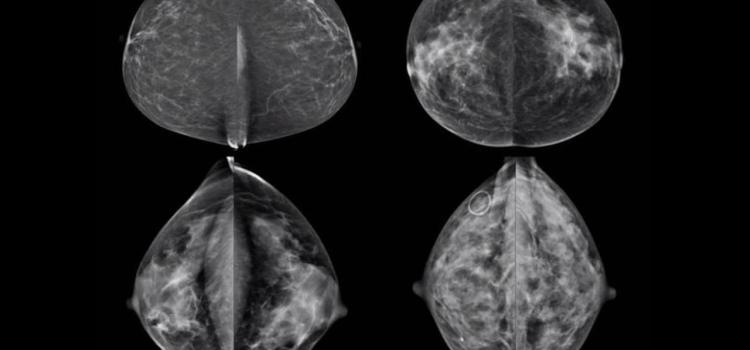

July 29, 2025 — A new technology that harnesses AI to analyze mammograms and improve the accuracy of predicting a woman’s personalized five-year risk of developing breast cancer has received Breakthrough Device designation from the Food and Drug Administration (FDA).

Mammography is one of the great triumphs of innovation in breast cancer care, as it is the only screening technology ...

Headlines around the world the past several months declared that artificial intelligence (AI) is better at detecting ...